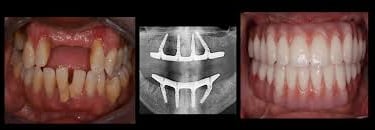

Implant restorations